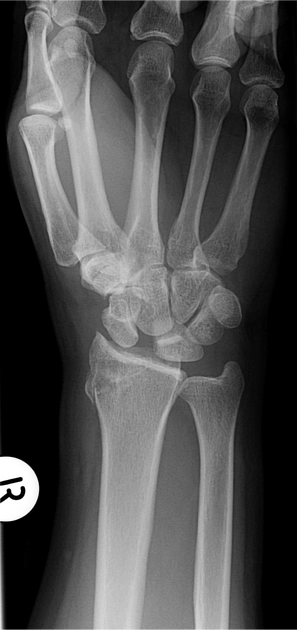

Các khoang duỗi cổ tay (Extensor compartments of the wrist)

16/03/2026